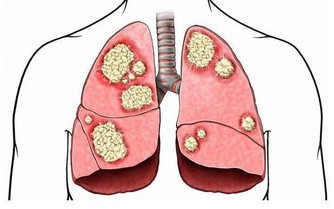

5. 尿毒症:憋尿也可能使得尿液回流到腎臟,造成腎積水引起尿毒症等嚴重後果,恐造成腎臟永久性的傷害。